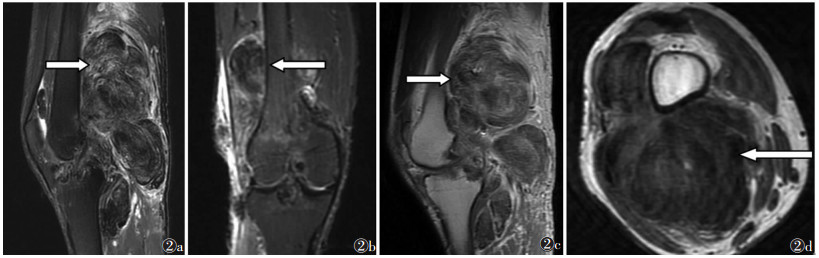

| 图 2 男, 31岁, 色素沉着绒毛结节滑膜炎 图2a~2d 分别为矢状位FS-T2WI、冠状位FS-T2WI、增强矢状位T1WI及横断位T1WI图像, 增生滑膜内出现绒毛、结节状T1WI等或低信号, T2WI呈低信号含铁血黄素沉着, 增强扫描含铁血黄素结节在强化滑膜衬托下呈低信号, 病变跨关节滑膜囊内外生长, 同时伴关节面软骨、软骨下骨浸润及骨髓水肿 |

2.2 滑膜病变形态及MRI信号5例树枝状脂肪瘤患者滑膜肥厚、呈树枝或海草样弥漫性增生, T1WI呈等信号、FS-T2WI等或稍高信号, 增生肥厚滑膜内见多发类圆形或类椭圆形、与皮下脂肪层一致的T1WI呈高信号、FS-T2WI低信号(图 1)。10例色素沉着绒毛结节滑膜炎滑膜肥厚呈绒毛或结节样弥漫增生, T1WI呈等或低信号、T2WI呈低信号, 增强扫描明显不均匀强化; 增生滑膜内可见T1WI及FS-T2WI均呈低信号的含铁血黄素结节, 增强扫描在强化滑膜衬托下呈低信号(图 2a~2c)。

2例树枝状脂肪瘤增厚滑膜侵蚀关节面软骨, 致关节面不光整、稍毛糙, 局部关节面下骨质见斑片状T1WI呈低信号、FS-T2WI高信号软骨下骨损伤表现。7例色素沉着绒毛结节滑膜炎均出现不同程度的关节面软骨及软骨下骨浸润, 关节面毛糙、不光整, 关节面凹陷, 伴结节状、T1WI及FS-T2WI均呈低信号的含铁血黄素结节, 部分结节与滑膜相连, 结节边缘见少许条片状T1WI呈低信号、FS-T2WI高信号骨髓水肿表现(图 2d)。15例均出现不同程度关节囊内积液, 5例色素沉着绒毛结节滑膜炎患者同时伴腘窝积液, 积液范围与增生肥厚滑膜分布一致。